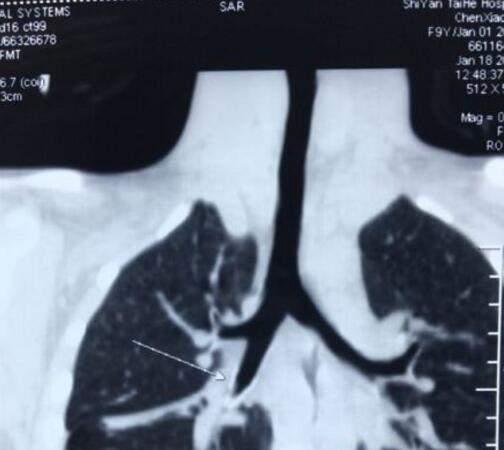

太和医院专家一看,发现晓慧随着呼吸,肺部可以听到像吹哨子一样的声音,怀疑是不是气管里有问题。拍片子后更是大吃一惊!

拍片后发现晓慧的支气管被异物卡住

原来,晓慧的右侧支气管里面有一个圆锥状的异物,把支气管给卡住了。不过,幸亏异物中间有个小孔,还可以通气,才不至于让小孩出现呼吸困难。